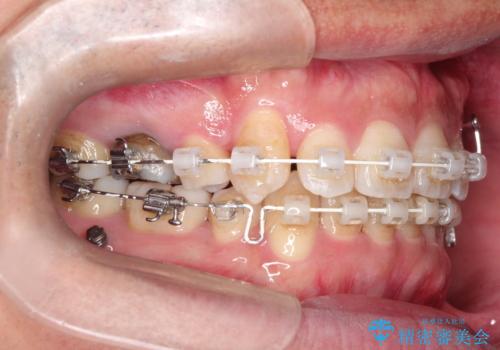

- 審美装置(ブラケット:白/ワイヤー:白)

- 2年3ヶ月

スペースの不足量が多く、抜歯を伴うワイヤー矯正にて治療を行いました。

若干の口元の突出感もあったため、抜歯によるスペースを利用し、がたつきの改善と前歯の後退をを行いました。